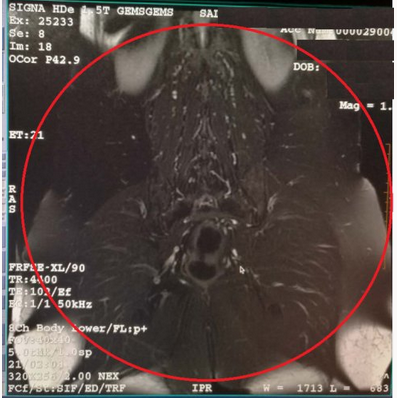

上面的图片,可以清楚的看到,在红圈内部磁场是十分均匀的,超出了红圈,磁场的均匀性就急剧变差了。

GE的磁体可以保证45cm直径内磁场的均匀性,与机器设计的最大FOV是48cm对应,能满足绝大部分部位成像的要求。